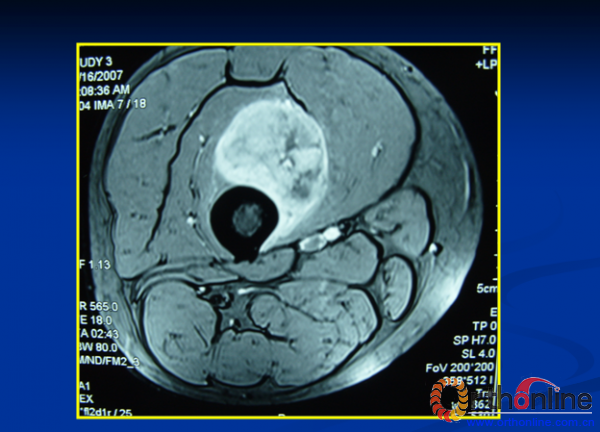

2013-10-10 文章来源:北京大学肿瘤医院骨与软组织肿瘤科 白楚杰 我要说